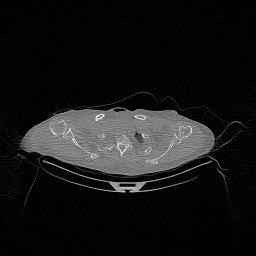

The results for simulated noisy data are shown in Fig. 2. The first and third rows display two representative slices from the test set, and the second and fourth rows present the corresponding error maps. The traditional WCE method suppresses cupping artifacts and recovers some missing anatomical structures but still shows noticeable deviations from the ground truth. Predictions from the four diffusion-based models demonstrate a markedly improved ability to restore anatomical structures. Among them, cDDPM fails to fully reconstruct the patient bed and retains residual noise in its outputs. This noise is attributable to an incomplete reverse denoising process rather than residual Poisson noise, as evidenced in our noise-free experiments (Fig. 5 in the Appendix). PatchDiffusion, diffusionGAN, and I2SB achieve similar visual quality, with I2SB producing the cleanest and most consistent reconstructions.

Quantitative results in Tab. V further confirm I2SB’s superiority over conventional deep learning methods such as FBPConvNet and Pix2pixGAN across RMSE, PSNR, and SSIM. Compared to other diffusion models—including cDDPM, PatchDiffusion, and cLDM—I2SB delivers higher image quality, while diffusionGAN achieves comparable quantitative performance. However, I2SB demonstrates a significant advantage in inference efficiency, as summarized in Tab. IV.

The experimental results on clinical head data are shown in Fig. 4. The reference images were reconstructed using the fast iterative shrinkage-thresholding algorithm (FISTA) with total variation regularization from non-truncated projection data. In the WCE reconstructions (Fig. 4(b)), severe truncation prevents accurate recovery of anatomical structures outside the FOV. Despite being trained solely on simulated data with a domain gap, all deep learning models can restore a substantial portion of the missing anatomy. Among them, the diffusion-based methods recover soft-tissue boundaries more faithfully than the conventional deep learning approach FBPConvNet, highlighting their stronger image generation capability. However, cDDPM reconstructions exhibit more noticeable noise than those from other methods, consistent with the simulated data results. The patchDiffusion model introduces artifacts within the FOV, likely due to its patch-wise processing strategy. While I2SB shares the same limitations as other diffusion models in perfectly restoring soft-tissue detail, it produces fewer residual noise patterns and fewer artifacts within the FOV boundaries. Overall, Fig. 4 demonstrates the strong efficacy of I2SB in reconstructing real CBCT data.